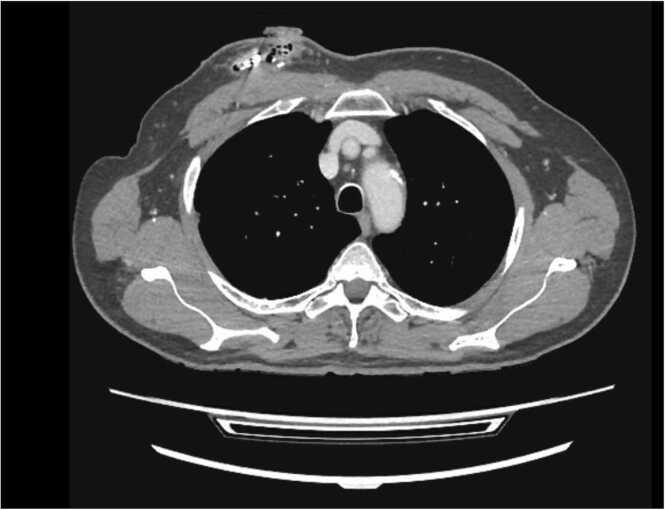

71-year-old male with history of obstructive sleep apnea presented with persistent drainage from the surgical incision site over the recently implanted hypoglossal nerve stimulator. Wound cultures from device pocket identified the pathogen as . Clinical course included treatment with broad-spectrum intravenous antibiotics and device explantation. This case is the first known device associated infection.

一名71岁男性,有阻塞性睡眠呼吸暂停病史,近期植入舌下神经刺激器后手术切口部位持续引流。从装置袋采集的伤口培养物鉴定病原体为……。临床过程包括使用广谱静脉抗生素治疗和取出装置。该病例是首例已知的与装置相关的感染。